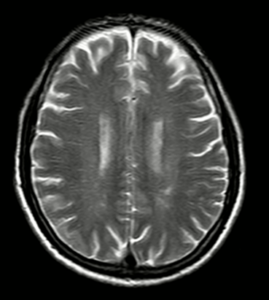

CASE LÂM SÀNG: ĐIỀU TRỊ BỆNH NHÂN MẮC HAI LOẠI UNG THƯ: UNG THƯ HẮC TỐ TÁI PHÁT DI CĂN VÀ UNG THƯ BIỂU MÔ TẾ BÀO GAN TẠI TRUNG TÂM Y HỌC HẠT NHÂN VÀ UNG BƯỚU, BỆNH VIỆN BẠCH MAI. GS.TS. Mai Trọng Khoa, BSNT. Nguyễn Văn Tiến,...